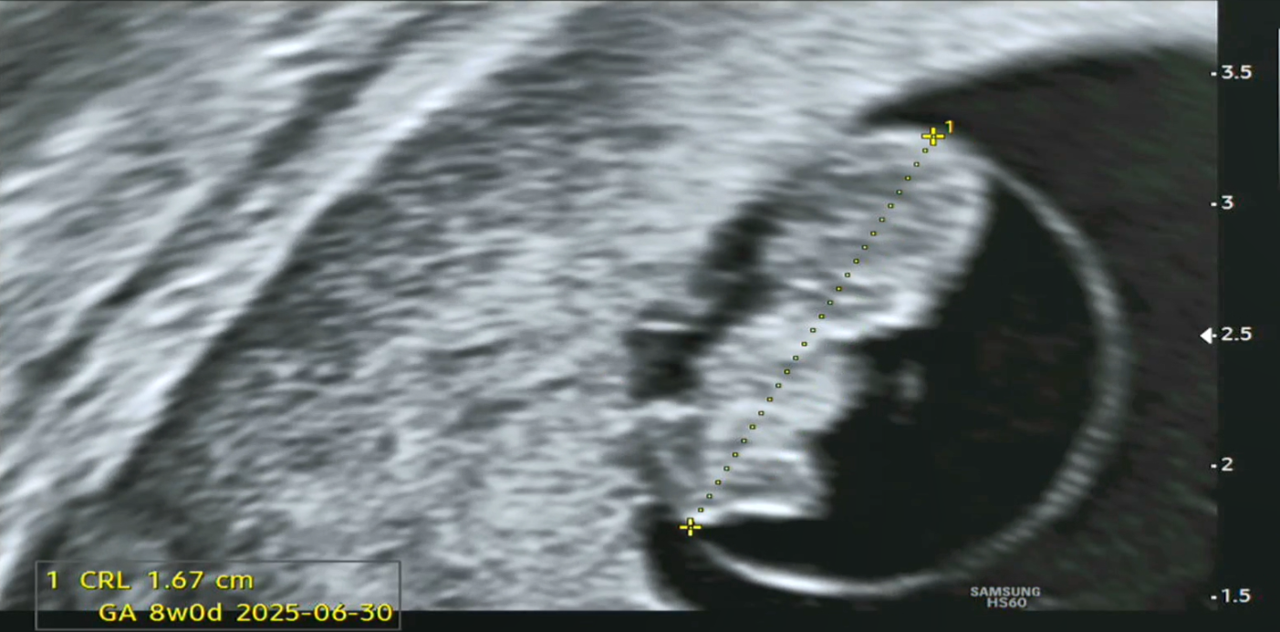

임신 8주 차 아기의 크기가 1.5~1.6cm 정도로 성장한다고 하는데, 우리 '팡팡이'는 1.67cm라 딱 주수에 맞게 크고 있다고 하네요. 그리고 심장박동수도 점차 증가하여 9주까지는 160~180 bpm 정도라고 하는데, 현재 171 bpm이니 정상이라고 합니다(인터넷에서 검색해 보니 조금씩 다르게 수치가 나오기는 하더라고요).

7주0일 몸길이.png

[왼쪽-태아 심장박동수(171 bpm), 오른쪽-태아 크기(1.67 cm)]